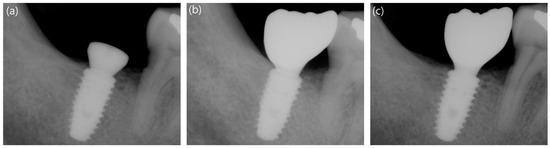

2.3.5. Measurement of Marginal Bone Loss

3.4. Comparison of Marginal Bone Loss between the Long and Short Implants

| 12-week follow up | Mesial | −0.22 ± 0.98 | -0.15 ± 0.79 | 0.893 |

| Distal | 0.08 ± 0.81 | 0.20 ± 0.78 | 0.728 | |

| Avg. | −0.07 ± 0.78 | 0.03 ± 0.63 | 0.885 | |

| 48-week follow up | Mesial | −0.15 ± 0.94 | -0.13 ± 0.82 | 0.719 |

| Distal | 0.27 ± 0.80 | 0.23 ± 0.92 | 0.573 | |

| Avg. | 0.06 ± 0.82 | 0.05 ± 0.77 | 0.655 | |